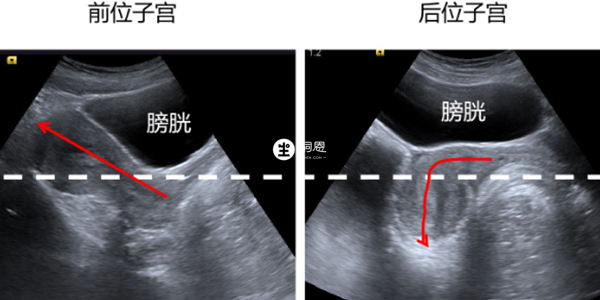

子宮前位是指子宮體走形向前指向陰道後穹隆,前位子宮更靠近肚皮。而後位子宮宮體向後走形,子宮位置更靠近臀部。而陰超檢查子宮是婦科超聲中最常用的方法,有經陰道和經腹部檢查,子宮前位和後位在這兩種B超檢查下區別如下:

2、而對於經腹部的婦科超聲檢查,以宮頸處的中線為標準(虛線),宮腔線(紅線)在中線上方的為前位子宮,宮腔線在中線下方的為後位子宮。

後位子宮,因為它是向下傾的,距離腹部面板是較前位子宮遠的。而對於經腹部檢查,它的穿透力是有限的,後位子宮因為位置深、更容易受到腸氣的影響顯示多數沒有前位子宮清楚,後位子宮對於膀胱憋尿有更高的要求。而對於陰超來說,前位子宮和後位子宮的顯示基本沒有差別,而且也不用憋尿。